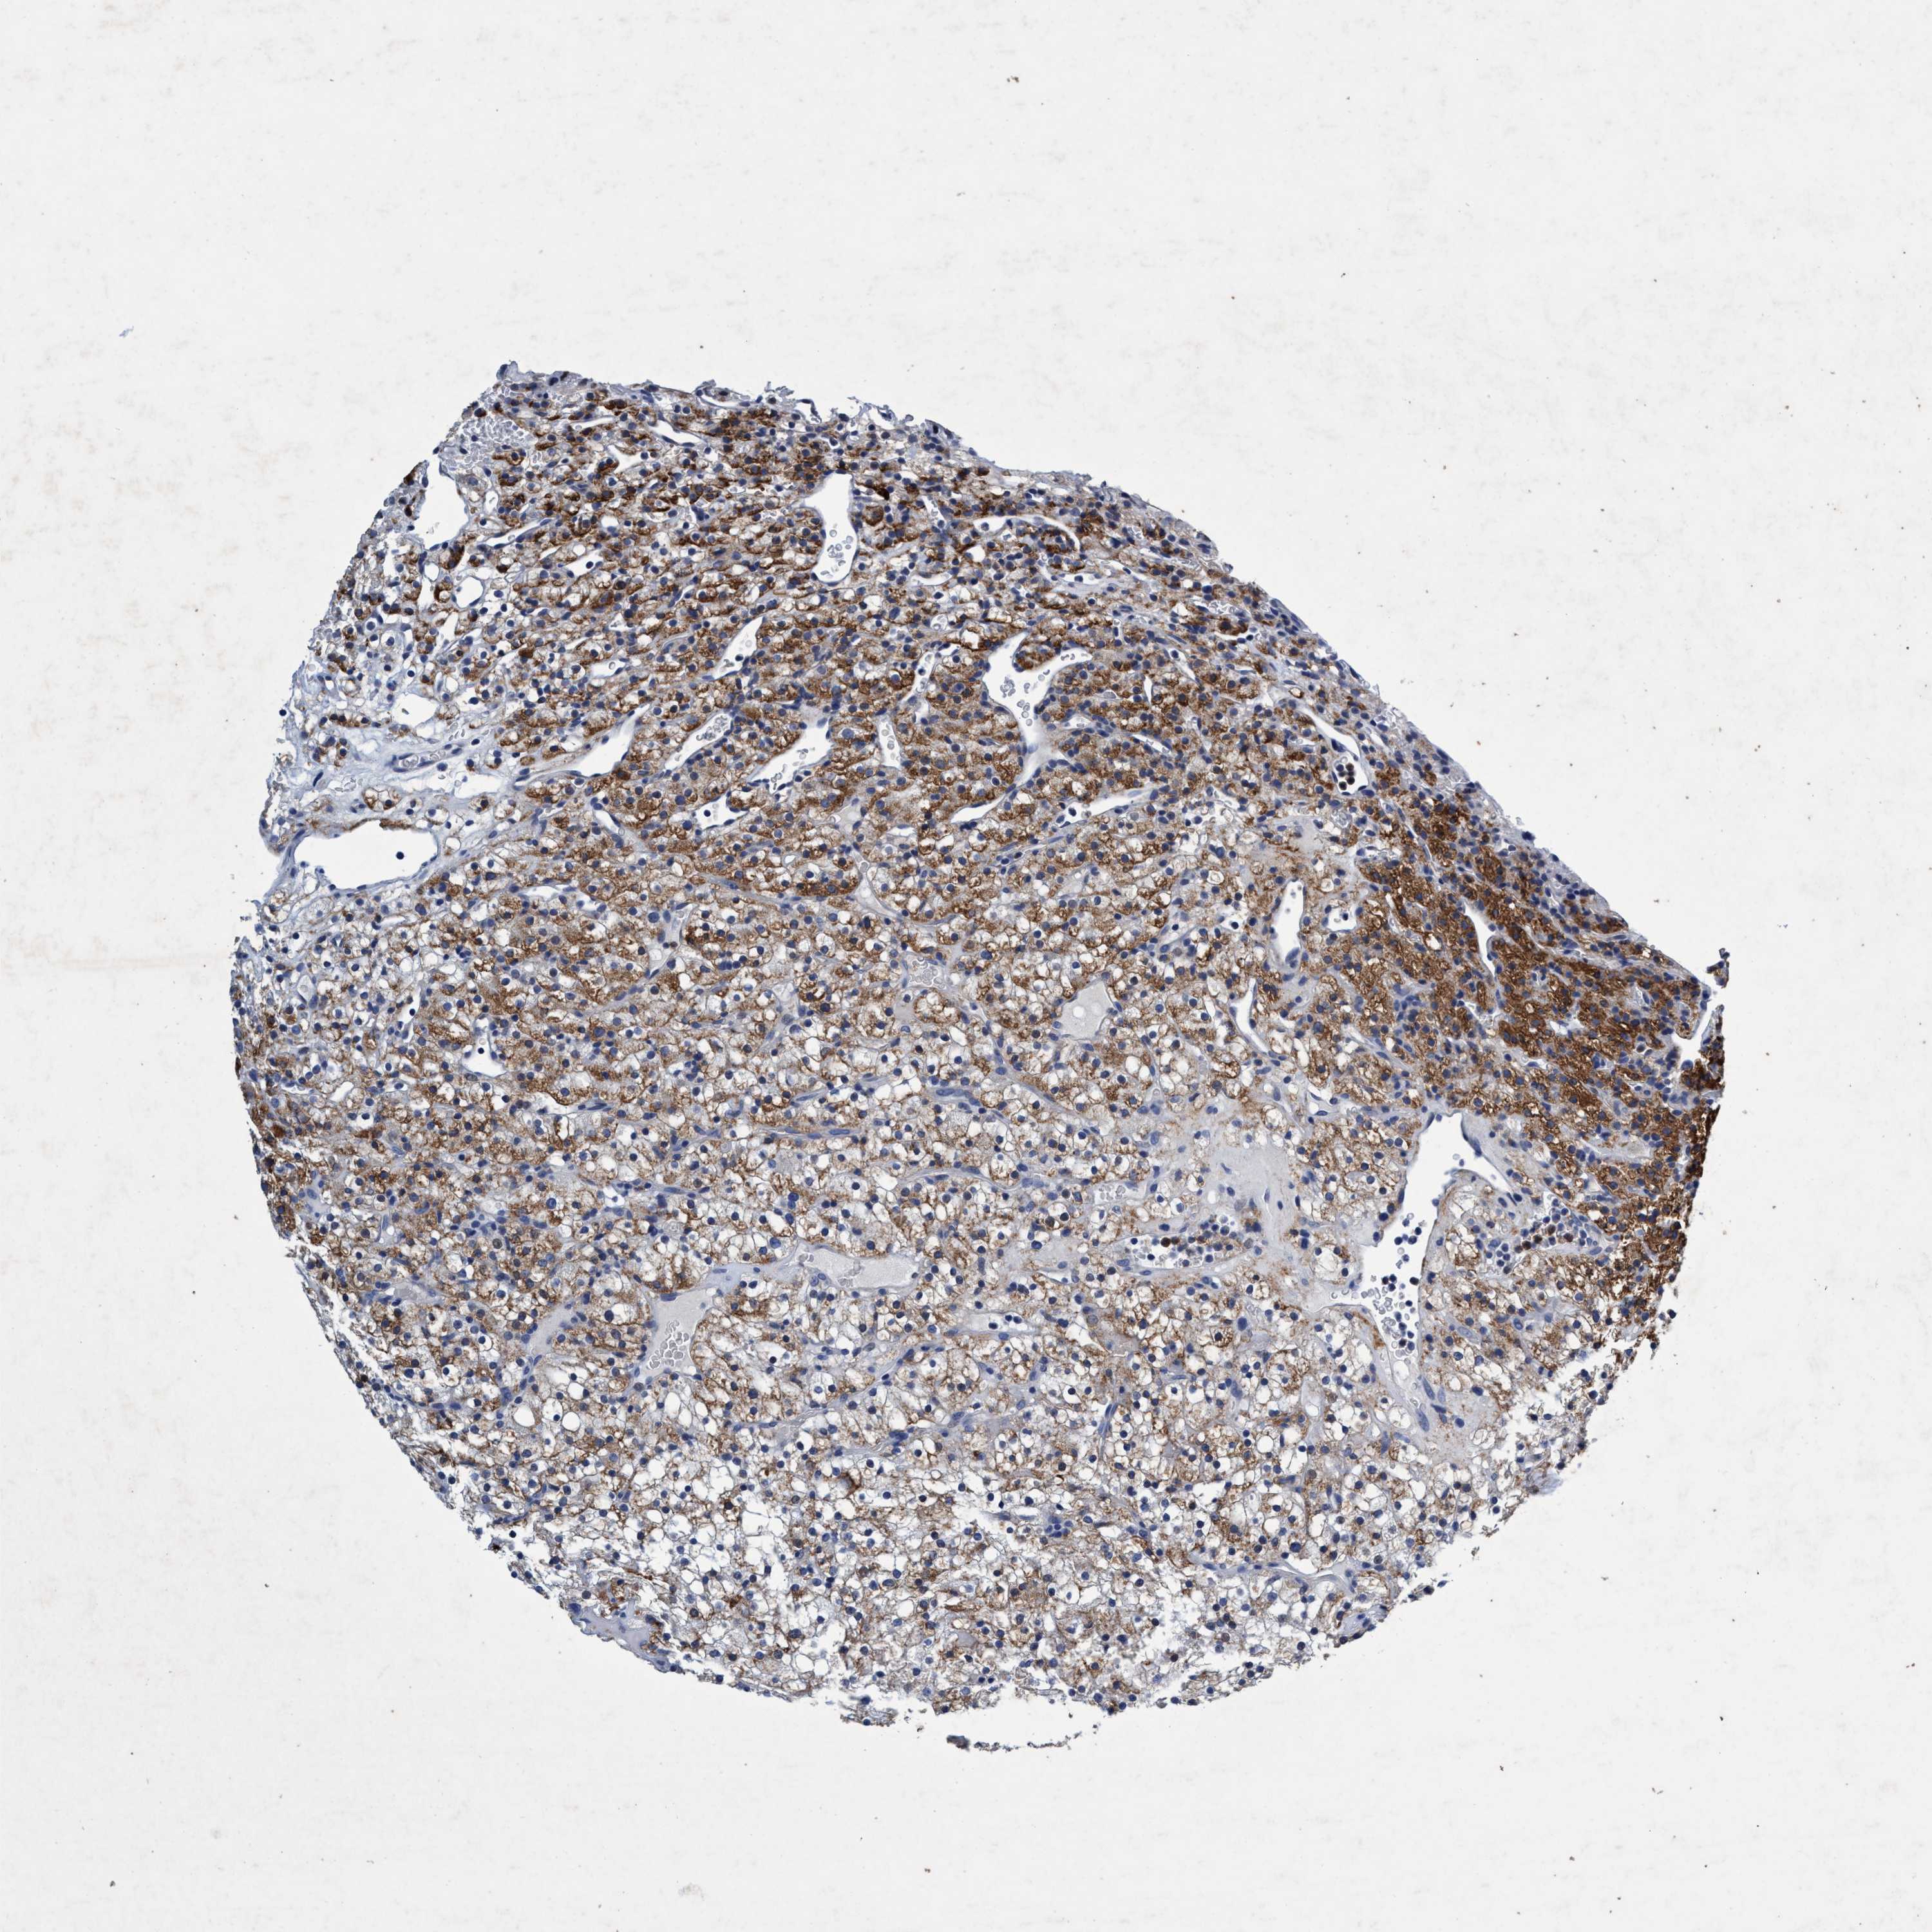

KIDNEY RENAL CLEAR CELL CARCINOMA (TCGA) - Interactive survival scatter ploti

& Survival analysisi

GRB14 is potential prognostic, high expression is favorable in Kidney Renal Clear Cell Carcinoma (TCGA)

: 1.01

Average pTPM 1.8

Number of samples 521